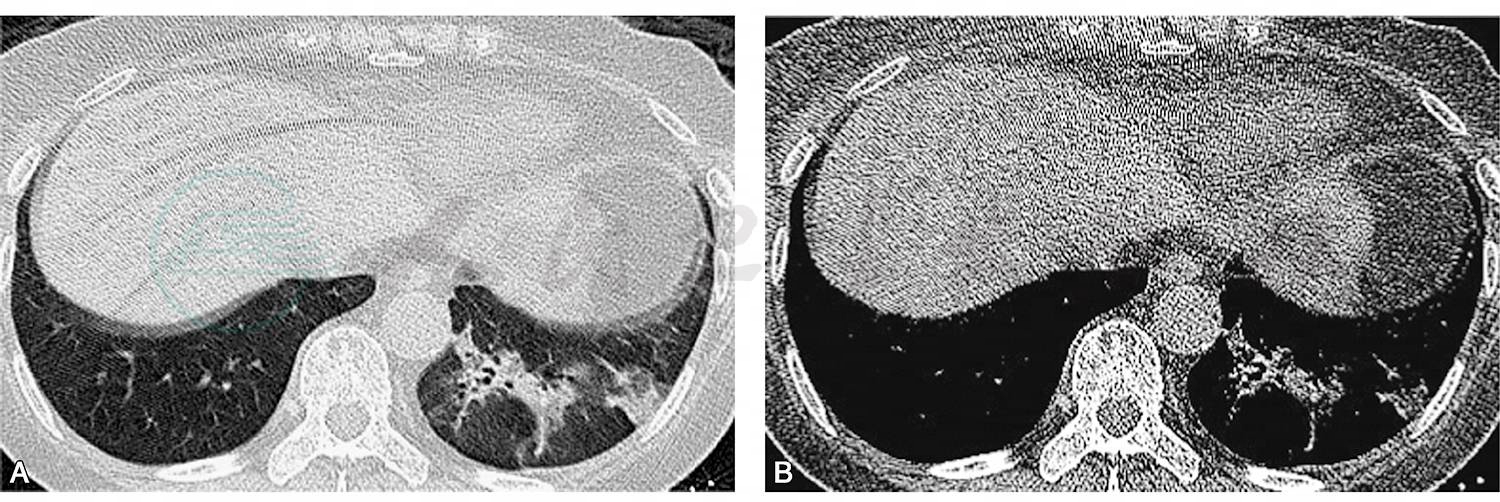

胸部CT扫描(2017-05-12):左肺下叶基底段磨玻璃影、实变影伴空泡征(图1)。

图1 胸部CT示左肺下叶基底段近膈顶处磨玻璃渗出影、实变影伴空泡征(A);纵隔窗相应部位可见软组织影(B)